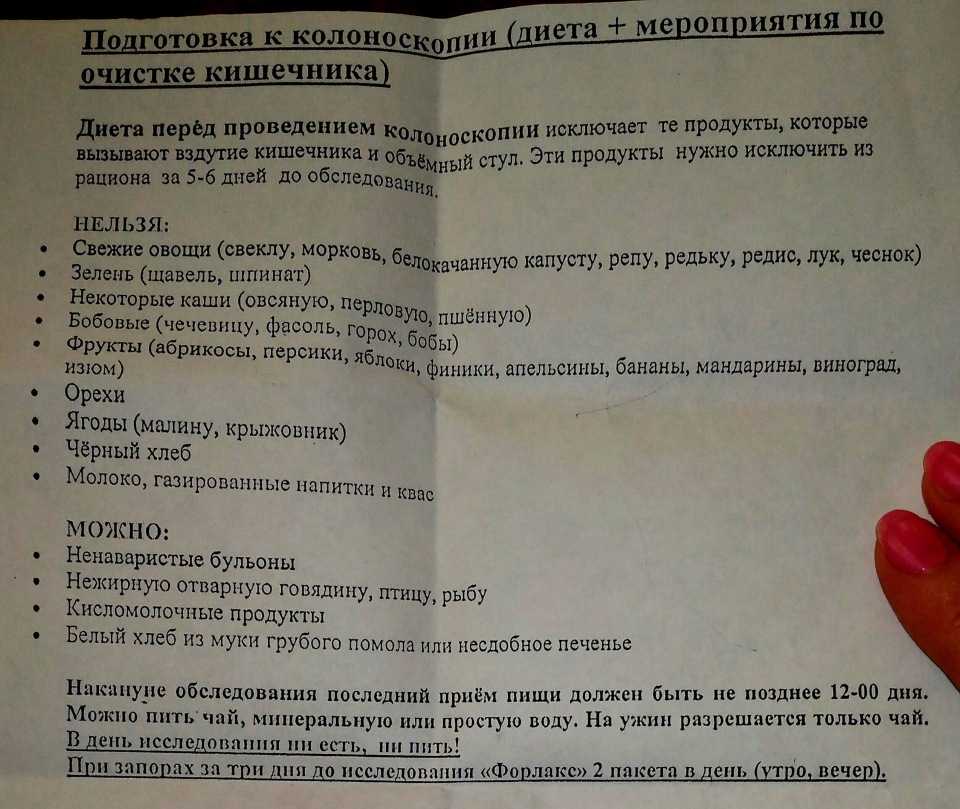

Подготовка к ирригоскопии: необходимые препараты